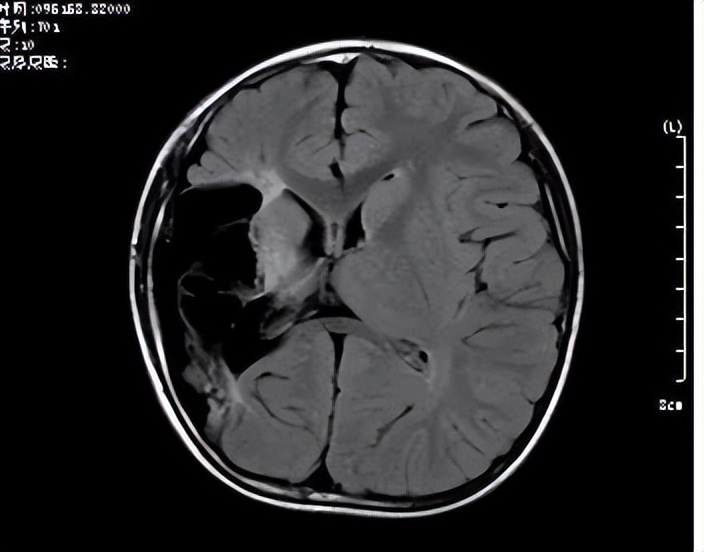

:“头部核磁提示孩子右侧大脑软化灶、脑萎缩,结合脑电图,癫痫样放电也全在右侧大脑,纤维束成像结果显示右侧纤维束明显减少,那么选择右额顶开颅大脑半球离断术,右侧大脑功能部分被左侧代偿,对功能影响不大,又能控制住癫痫发作,这也是难治性癫痫的有效方法。”

术前检查